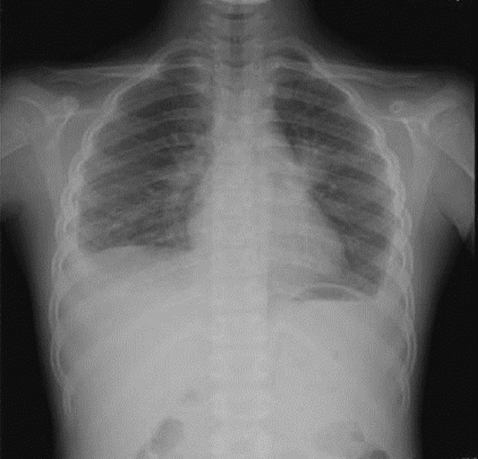

On admission, her vital signs were as follows: body temperature, 37.8℃; heart rate, 90/min; respiratory rate, 24/min; and blood pressure, 100/70 mmHg. On examination, she looked very ill and her breathing sounds were decreased on both sides of the lower chest. Moderate tenderness was detected in the right flank and the right inguinal area. A chest radiograph indicated pleural effusion (Fig. 1), and abdominal sonography revealed an inflammatory lesion in the right psoas muscle (Fig. 2). Her total white blood cell (WBC) count was 26,900 cells/mm3, hemoglobin level was 10.7 g/dl, erythrocyte sedimentation rate (ESR) was 75 mm/hr, and C-reactive protein concentration was 71 mg/dl. The patient also presented with hypereosinophilia (66%), and the total serum IgE value higher than 2,500 IU/ml. Because her dietary history and laboratory findings were indicative of a parasitic infection, we performed a serum antibody test using ELISA and examined her stool, sputum, and pleural fluid specimens [11]. No evidence of parasite eggs in the stool or sputum specimen was obtained, but ELISA was positive for P. westermani in the serum, with an optical density (OD) of 0.619 (cut-off OD: 0.255). The pleural fluid obtained by thoracentesis revealed the following findings: WBC, 26,200 cells/mm3 (neutrophils, 25%; lymphocytes, 72%); pH, 7.129; proteins, 8.2 g/dl; albumin, 2.1 g/dl; glucose, 5 mg/dl; and turbid appearance. Gram staining, culture studies, and tuberculosis- PCR (TB-PCR) in the pleural fluid, however, were negative.

One month after the first admission, the eosinophil count in the peripheral blood and the total serum IgE value were still high (eosinophils, 37.4%; IgE, 1,094 IU/ml). The follow-up chest radiograph showed improvements of the left pleural effusion, but persistence of the right pleural effusion (Fig. 3A). She was, therefore, readmitted to the hospital, and the pleural fluid was drained using a pigtail catheter.

Analysis of the drained pleural fluid showed the following results: WBC, 250 cells/mm3 (neutrophils, 8%; lymphocytes, 49%); pH, 7.164; protein, 9.8 g/dl; albumin, 2.7 g/dl; glucose, 4 mg/dl; and amber colored appearance. Gram staining and culture studies of the pleural fluid were negative, but P. westermani-specific IgG antibody was strongly positive in the pleural fluid, with an OD of 1.576 (cut-off OD: 0.002). Abdominal sonography revealed a smaller, albeit still existing, inflammatory lesion in the right psoas muscle (Fig. 3B). The patient was treated again with a third cycle of praziquantel therapy. After 4 days, the catheter for draining pleural fluid was removed, and she was discharged.

The major symptoms of paragonimiasis are cough, hemoptysis, and dyspnea; some of these overlap with symptoms of tuberculosis and other pulmonary disorders. Pulmonary infiltrates, effusion, nodules, or lesions are also very common [14, 15], and ectopic locations of flukes include the pleura, abdominal wall, viscera, and brain. In our case, the patient complained of abdominal pain, especially in the right flank and right inguinal area but had no cough, dyspnea, or chest pain. The chest radiograph revealed pleural effusion, and abdominal sonography showed a low-echoic lesion with inflammation of the surrounding fat in the psoas mucle. This lesion is presumed to be due to adult flukes, which are present in loosely formed cysts in the psoas muscle.